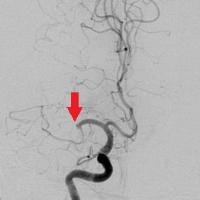

血栓回収療法

術前

術後

脳の血管に血栓が詰まって血流が途絶えると、脳細胞は急速に壊死していき脳梗塞を起こします。

脳梗塞による重篤な後遺症をできるだけ回避できるよう、可能な限り早く詰まった血栓を取り除いて血流を再開させ、脳へのダメージを最小に抑えることを目的に行う治療です。

閉塞血管までカテーテルを進め、器具を用いて血栓を掻き出したり吸い出したりして取り除きます。